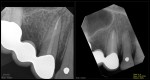

Entire buccal plate missing. CBCT at 5 years suggests most, but not all, bone has regenerated. As canine bridge abutment, it is subjected to some occlusal trauma. gbc